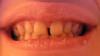

wel Опубликовано 13 марта, 2007 Поделиться Опубликовано 13 марта, 2007 Здравствуйте! У меня такая проблема: передние зубы до 5-к стоят с промежутками на обеих ч (наследственное от мамы). Кроме как психологического, никакого другого дискомфорта у меня до сих пор не было. Обратилась с консультацией к ортодонту. Выяснилось, что к тому же глубокий прикус. Рекомендуют брекеты (металлические или по моему выбору - эстетические) + накусочная площадка, ретенционный период и возможно еще виниры. Усечение уздечки тоже упоминалось. Направили на теленографию в боковой проекции. Вопросов много, буду рада даже если ответите на некоторые!Можно ли достигнуть желаемого рез-та только брекет системой? Совершенно не хочется лепить виниры на здоровые зубы из-за стирания эмали + окрашиваемость цемента и срока эксплуатации 10 лет (это если не будет сколов раньше…).Какие системы лучше, читала о Лингвальных брекетах и системе Damon 3. У мамы с возрастом щель между первыми резцами увеличивается, даже если мне сейчас все выровняют, не будет ли это временно, или ретейнеры мне пожизненно придется носить? Все зубы по высоте маленькие, особенно жевательные, не будет ли из-за этого проблемы с крепежом системы? Если знаете, посоветуйте специалиста в г Киеве? Ссылка на комментарий

wel Опубликовано 15 марта, 2007 Автор Поделиться Опубликовано 15 марта, 2007 Вобщем, вот что у меня вышло: Можно ли еще что-то добавить по моему вопросу? У Вас достаточно большие промежутки между зубами, после снятия брекетов требуется длительное ношение ретейнеров, не менее 10 лет. Иначе могут образовываться промежутки вновь. А что Вас смущает в несъемных ретейнерах? К ним быстро привыкают, они не доствляют дискомфорта. Только что заметила Ваш ответ! 10 лет... Не совсем знаю как они крепятся, почему-то кажется, что с ними нужен особый уход как с брекетами : чистка после каждого приема пищи и тд., иначе - КАРИЕС! Ссылка на комментарий